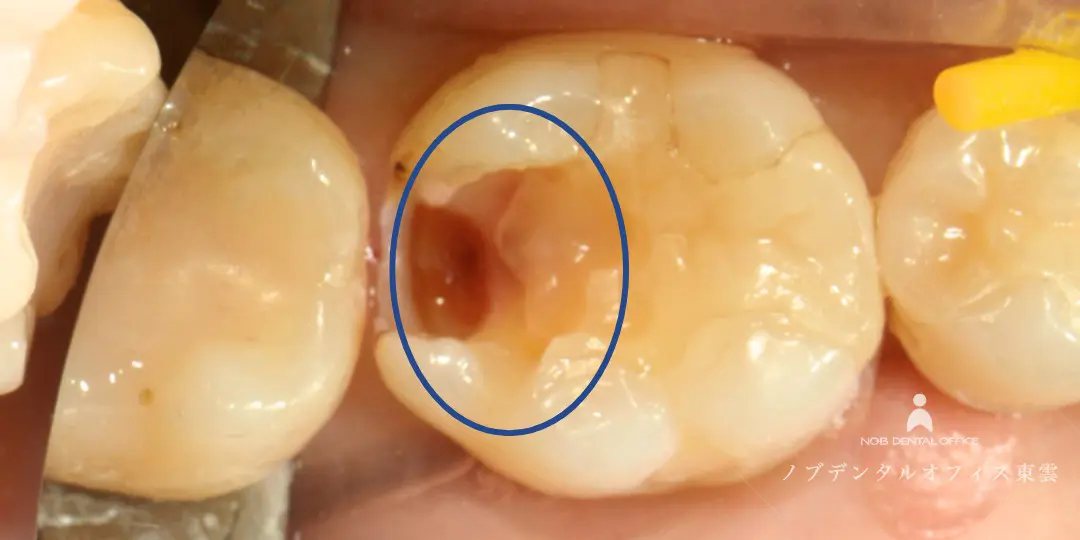

「奥歯に物が詰まる」とご来院。虫歯の再治療を行いました。

診察の結果、写真内・赤丸の歯はセラミック治療した歯なのですが、詰め物の奥に二次う蝕(虫歯)が認められました。

う蝕検知液で虫歯の部分だけを染め出し、健康な歯をできるだけ削らないよう注意して治療します。

虫歯の患部を丁寧に削った後は、CRで歯を保護し、ジルコニアインレーをセットします。

う蝕検知液で虫歯の部分だけを赤く染めた様子。

虫歯を取り除いた後、CRで歯を保護した様子